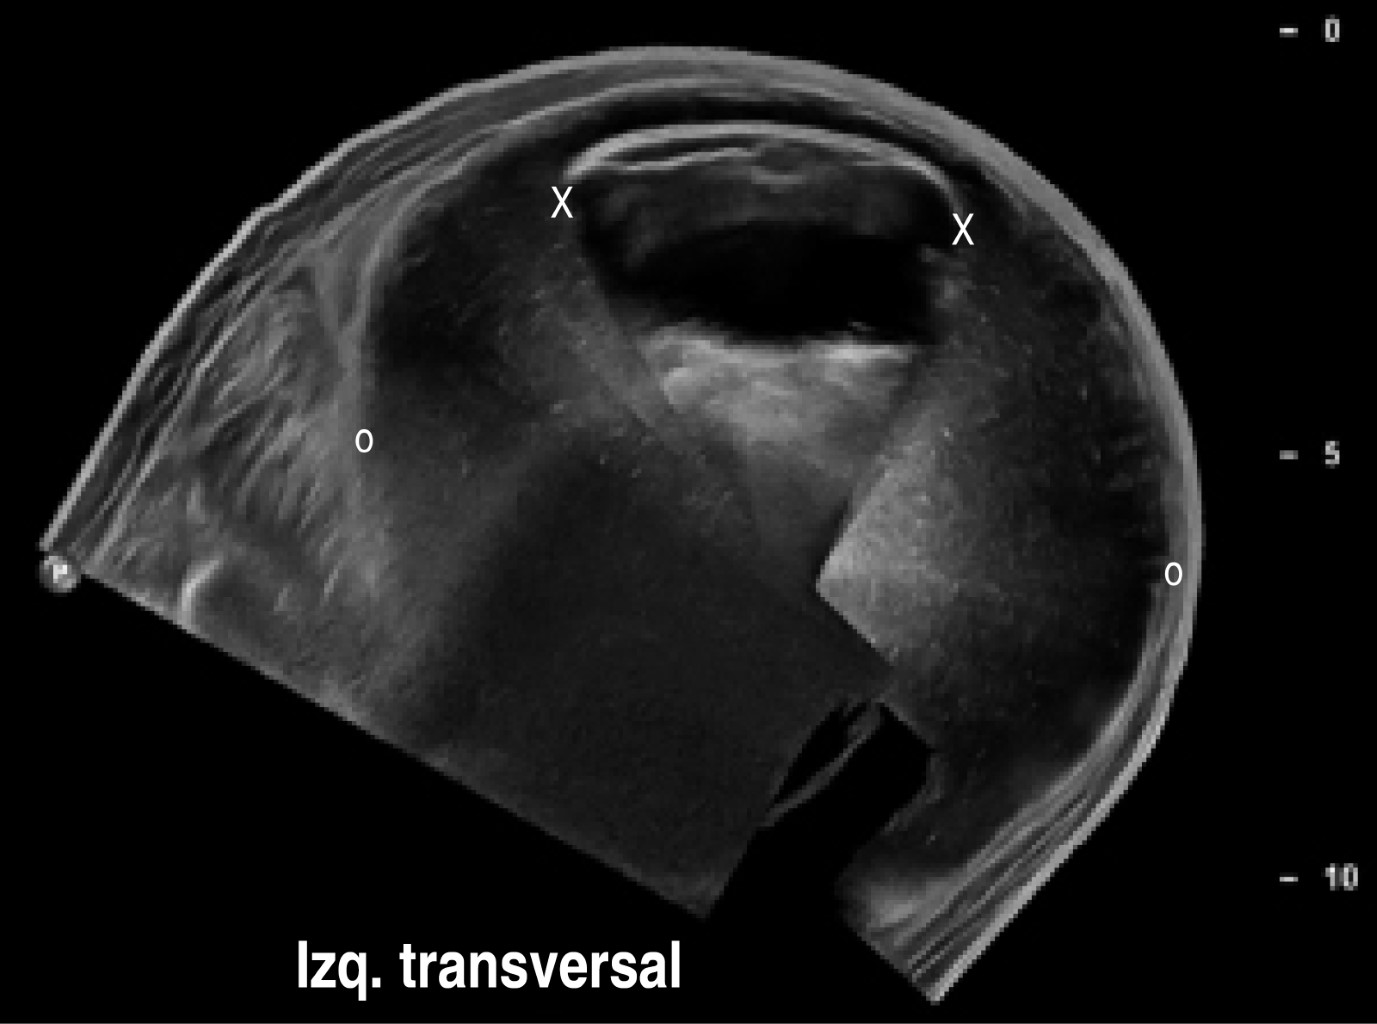

En el estudio de ultrasonido se encontró extensa colección líquida intracapsular de la pierna izquierda, sin descartar la ruptura del implante. El implante derecho con datos de ruptura y mínima colección.

Procedimiento quirúrgico (Figuras 1, 2, 3, 4 y 5):

El 24 de octubre se llevó a cabo el retiro del implante de la pantorrilla izquierda bajo anestesia local y sedación. El retiro del implante derecho se difiere para otro tiempo quirúrgico (dos meses) a petición de la paciente para que se facilitara su movilidad en el postoperatorio. En la imagen preoperatoria observamos el aumento de volumen de la pierna izquierda (Figura 6).